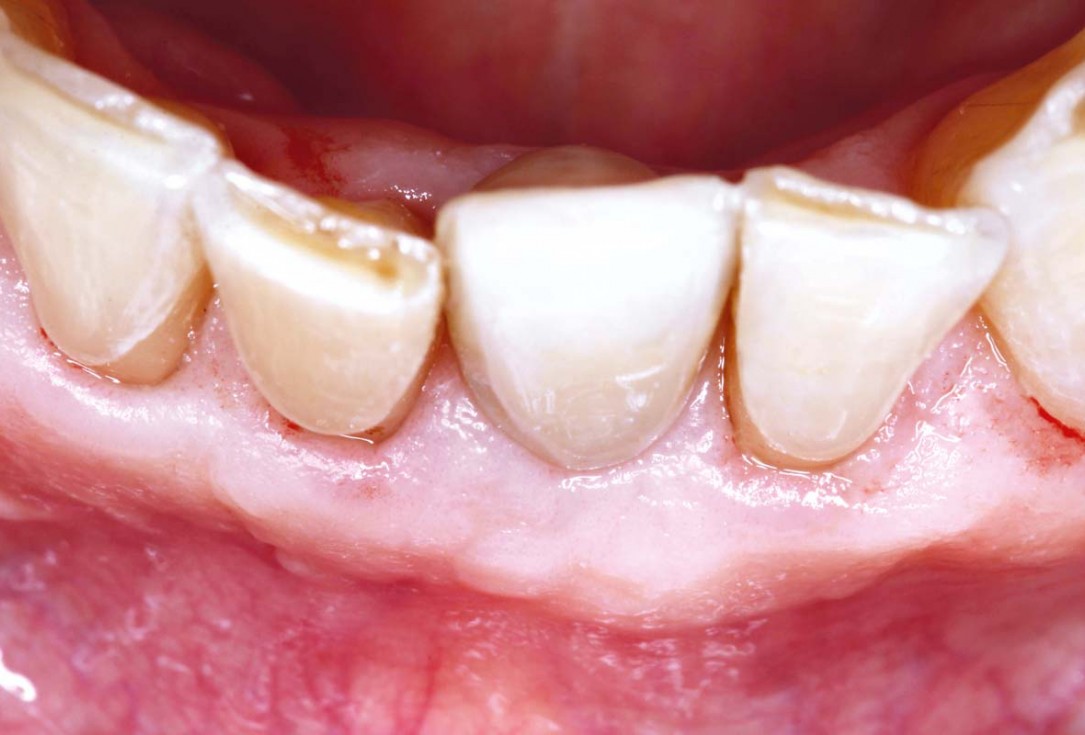

Initial view of the case. Discoloration of 1.1 and mild class I gingival recession